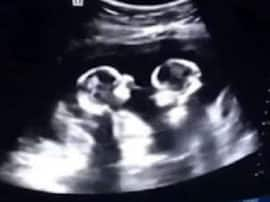

अलीगढ़, एबीपी गंगा। महिला अस्पताल में प्रसव के बाद संगीता को भले ही एक बच्चा सौंपा गया हो, मगर उसकी कोख में दो ही जुड़वा बच्चे ही पल रहे थे। संगीता का अल्ट्रासाउंड करने वाले दीनदयाल अस्पताल के रेडियोलॉजिस्ट डॉ. जगमोहन शर्मा ने पुलिस को ऐसा ही बयान दिया है। उन्होंने जुड़वा बच्चों वाली अपनी अल्ट्रासाउंड रिपोर्ट पर मुहर लगा दी है। रेडियोलॉजिस्ट के दावे से अस्पताल प्रबंधन की परेशानी बढ़ गई है।

पुलिस को दीनदयाल अस्पताल के रेडियोलॉजिस्ट डॉ. जगमोहन शर्मा ने बताया कि मैंने फरवरी व मार्च के बाद 26 मई को संगीता का अल्ट्रासाउंड किया। तीनों बार दो ही बच्चे दर्शाए गए और यही रिपोर्ट दी। हालांकि, केवल मेजरमेंट (आयु आदि) के लिए एक बच्चे का ही जिक्र किया, जिससे रिपोर्ट को त्रुटिपूर्ण मान लिया गया। रेडियोलॉजिस्ट का बयान लेकर पुलिस फिलहाल तो लौट गई, मगर अस्पताल प्रबंधन व स्टाफ की टेंशन बढ़ गई है।

रेडियोलॉजिस्ट डॉ. जगमोहन शर्मा ने बताया कि 'मैंने पुलिस को बताया है कि मेरी तीनों ही रिपोर्ट सहीं हैं, जिनमें संगीता को जुड़वा बच्चे बताए गए हैं। 26 मई को अंतिम अल्ट्रासाउंड के बाद क्या हुआ? इस बारे में कुछ नहीं कह सकता।'